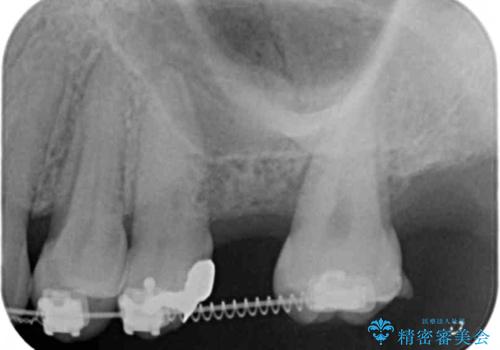

- 他院での矯正治療中、欠損した左上奥歯のインプラント治療を希望され来院されました。

最終的な歯の位置を矯正の担当医と綿密に相談しながら、インプラントの埋入部位を決定し治療にあたりました。

骨量が少なかったことから、上顎洞内へのソケットリフト方をインプラント埋入と同時に施行しています。